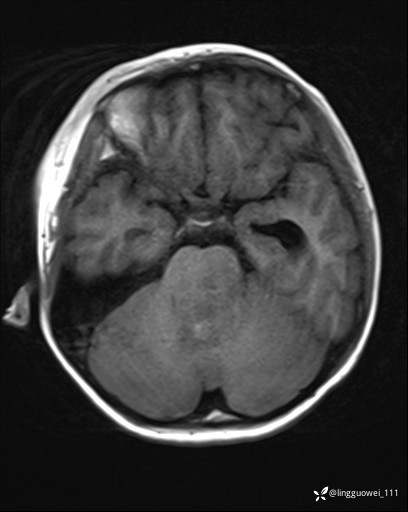

男,8岁,外伤后发现颅内占位,定位定性,4天后公布结果。

患者性别:男

患者年龄:8岁。

主诉:外伤后发现颅内占位。

外院做的手术,术后回本院复查,只有平扫,定位在哪?良性还是恶性?

T1